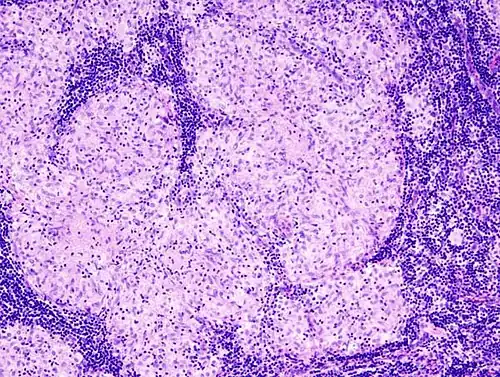

Histopathology

Sarcoidosis is characterized by the formation of non-necrotizing ("non-caseating") granulomas in various organs and tissues.[95] Giant cells, specifically Langhans giant cells, are often seen in sarcoidosis.[96] Schaumann bodies seen in sarcoidosis are calcium and protein inclusions inside of giant cells as part of a granuloma.[97] Asteroid bodies can be seen in sarcoidosis.[97] Hamazaki–Wesenberg bodies can be seen in lymph nodes and more rarely in lung biopsies with sarcoidosis and are inclusion bodies of lysosomes with protein, glycoprotein and iron.[98]

Sarcoidosis in a lymph node

Pulmonary sarcoidosis with granulomas with Langhans giant cells and asteroid bodies

Schaumann body in sarcoidosis

Asteroid body in sarcoidosis

Hamazaki–Wesenberg bodies in sarcoidosis in lymph node